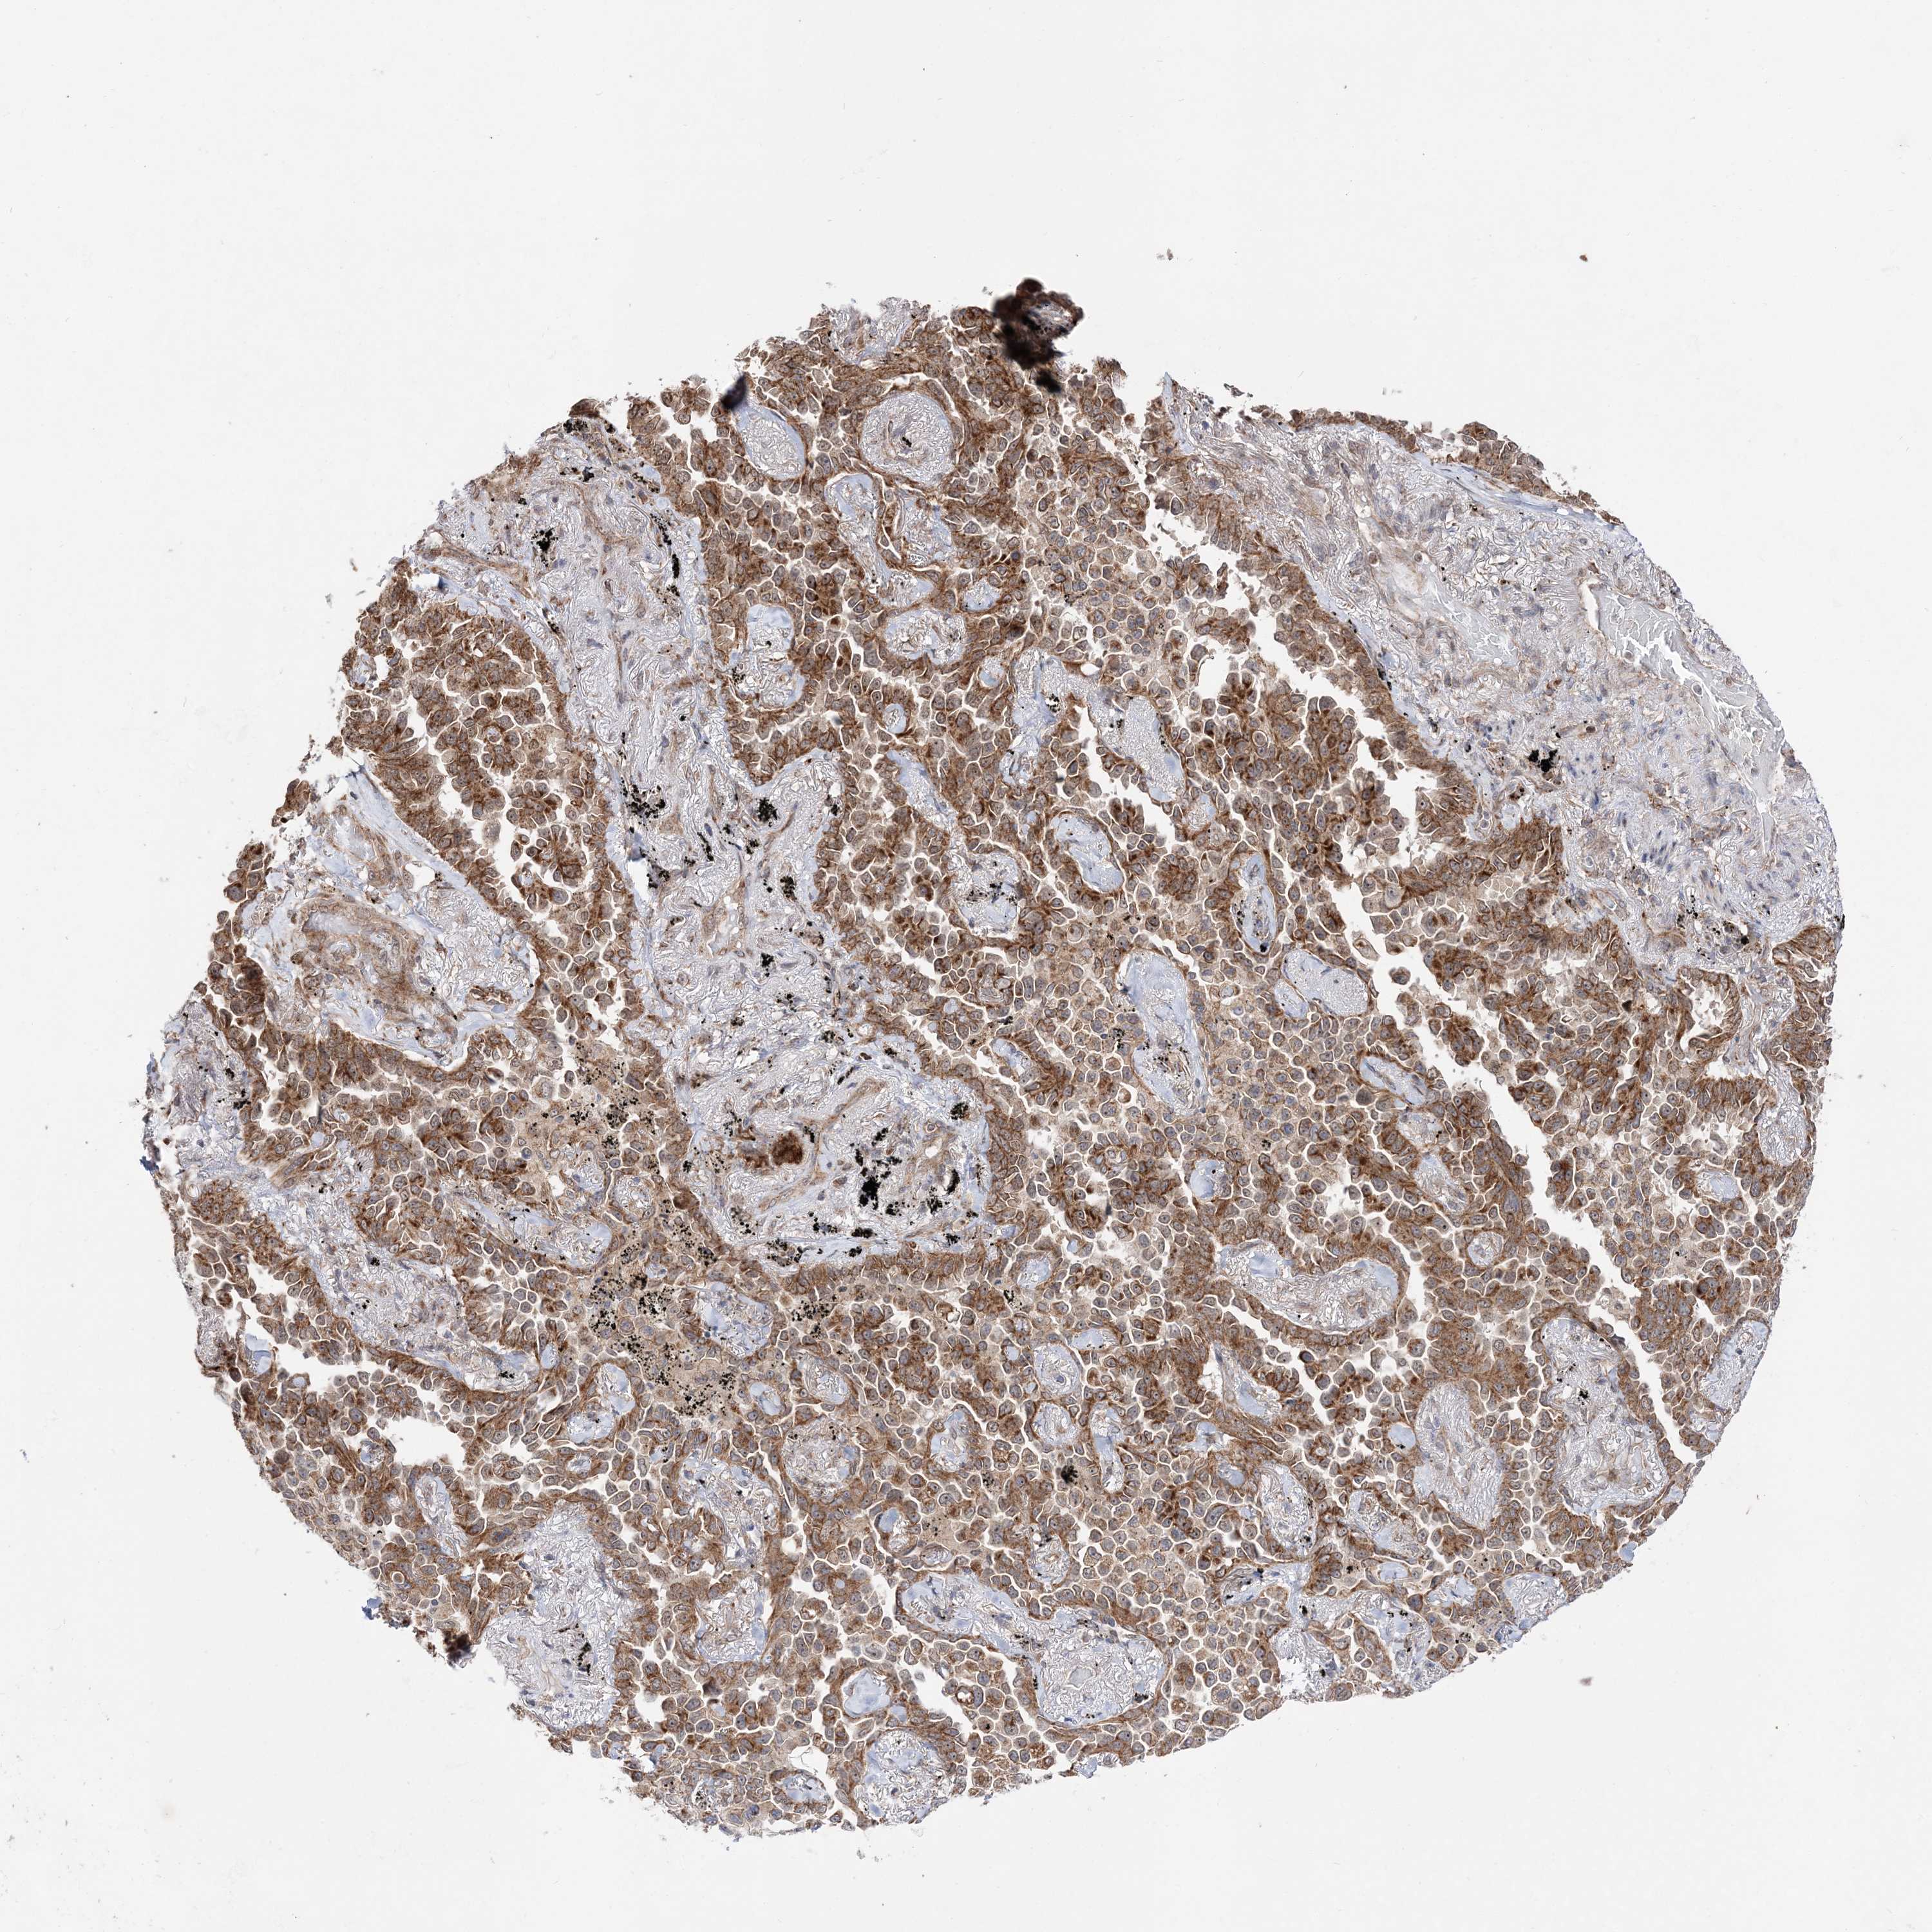

LUNG SQUAMOUS CELL CARCINOMA (TCGA) - Interactive survival scatter ploti

The Survival Scatter plot shows the clinical status (i.e. dead or alive) for all individuals in the patient cohort, based on the same data that underlies the corresponding Kaplan-Meier plots. Patients that are alive at last time for follow-up are shown in blue and patients who have died during the study are shown in red.

The x-axis shows the expression levels (FPKM) of the investigated gene in the tumor tissue at the time of diagnosis. The y-axis shows the follow-up time after diagnosis (years). Both axes are complimented with kernel density curves demonstrating the data density over the axes. The top density plot shows the expression levels (FPKM) distribution among dead (red) and alive patients (blue). The right density plot shows the data density of the survived years of dead patients with high and low expression levels respectively, stratified using the cutoff indicated by the vertical dashed line through the Survival Scatter plot. This cutoff is automatically defined based on the FPKM cutoff that minimizes the p-score. The cutoff can be changed by dragging the vertical line or by entering a cutoff value in the square labeled "Current cut-off".

Under the Survival Scatter plot the p-score landscape (black curve; left axis) is shown together with dead median separation (red curve; right axis). Dead median separation is the difference in median mRNA expression between patients who have died with high and low expression, respectively. It is calculated as follows: median FPKM expression of dead patients with high expression - median FPKM expression of dead patients with low expression. This is intended to aid the user in visually exploring custom cutoffs and the associated p-scores and dead median separation.

Individual patient data is displayed and can be filtered by clicking on one or more of the category buttons on the top of the page. Categories describing expression level and patient information include: high, low, alive, dead, female, male and tumor stages. The scale of the x-axis can be toggled between linear and log-scale by clicking on the "x log" button. Mouse-over function shows TCGA ID, patient information and mRNA expression (FPKM) for each patient.

& Survival analysisi

Kaplan-Meier plots summarize results from analysis of correlation between mRNA expression level and patient survival. Patients were divided based on level of expression into one of the two groups "low" (under cut off) or "high" (over cut off). X-axis shows time for survival (years) and y-axis shows the probability of survival, where 1.0 corresponds to 100 percent.

DALRD3 is not prognostic in Lung Squamous Cell Carcinoma (TCGA)

: 14.38

P scorei

N/A

Average pTPM 13.7

Number of samples 489